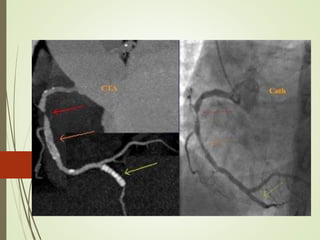

Inter arterial course of anomalous RCA originating from left sinus

Inter arterial courseof anomalous RCA originating from left sinus